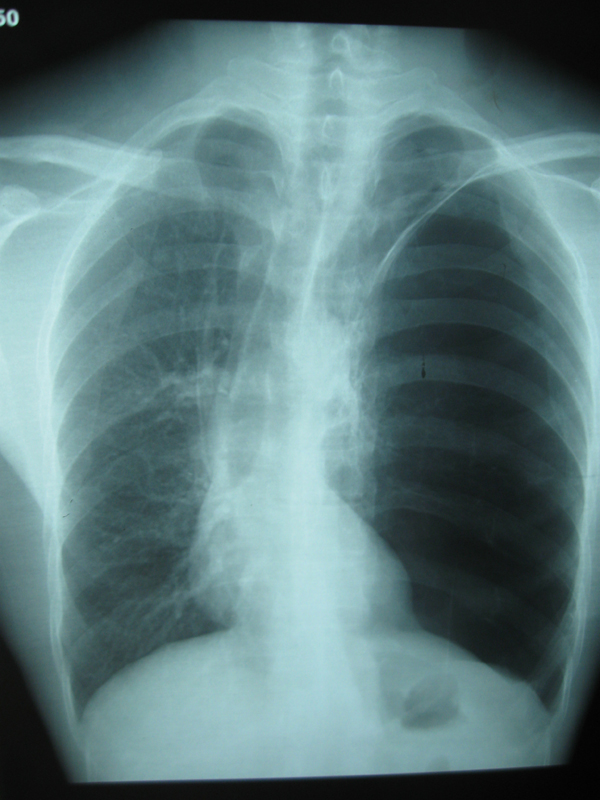

多例典型肺大泡的dr片与大家分享